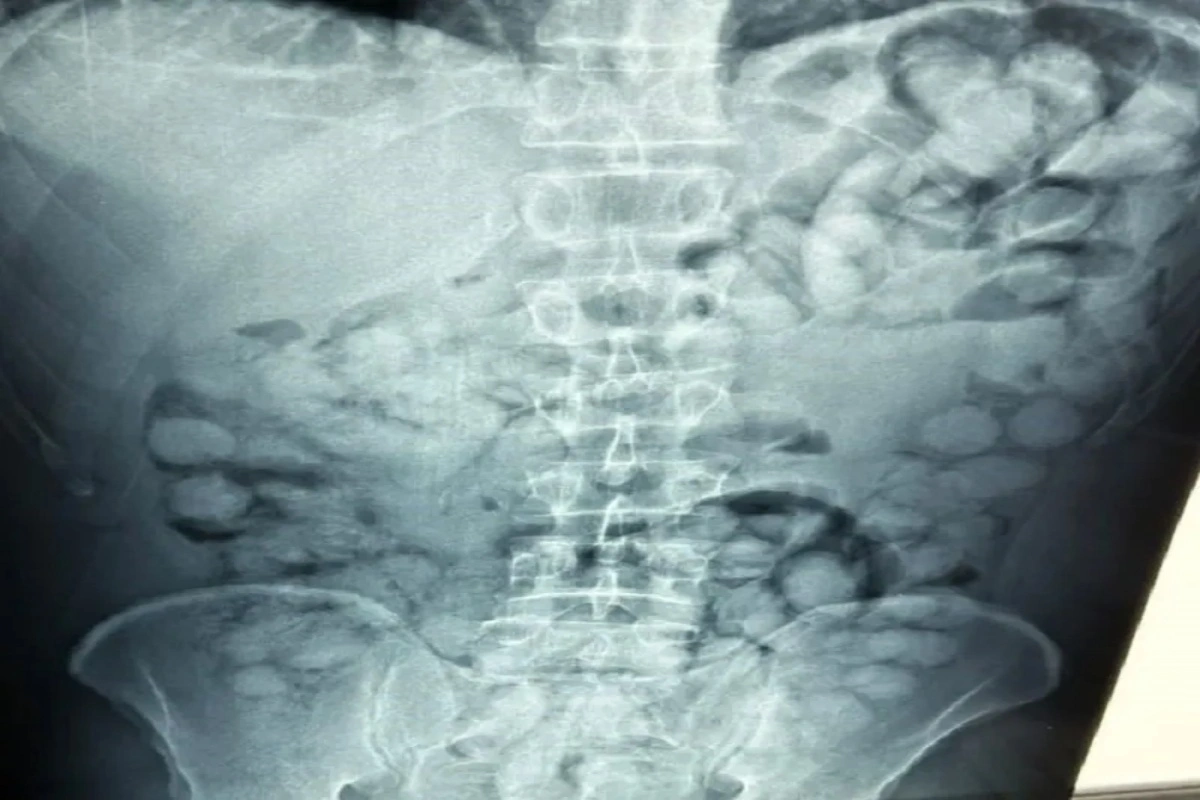

Ο άνδρας που ταξίδευε από Βραζιλία μέσω Γαλλίας, είχε καταπιεί 100 συσκευασίες κοκαΐνης. Η κάθε συσκευασία ήταν 10 γραμμαρίων και καθαρότητας 90%.